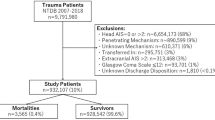

All adult patients registered in the TQIP database between 2013 and 2017 who suffered an isolated severe TBI, defined as a head AIS ≥ 3 with an AIS ≤ 1 in all other body regions, were included. Patients were excluded if they had a head AIS of 6. The association between different RCRI scores (0, 1, 2, 3, ≥ 4) and in-hospital mortality was analyzed using a Poisson regression model with robust standard errors while adjusting for potential confounders, with RCRI 0 as the reference.

The need for approval by the institutional review board was waived for this study since it only made use of retrospective anonymized data. The Declaration of Helsinki and the Strengthening the Reporting of Observational Studies in Epidemiology (STROBE) guidelines were adhered to throughout its completion [22]. All data were obtained from the American College of Surgeons Trauma Quality Improvement Program (TQIP) database, a national multi-institutional database of all trauma patients collected from more than 850 participating trauma centers across the United States. This database is gathered for risk-adjusted benchmarking and quality improvement. Furthermore, well-trained data registrars amass more than 100 patient-related and center-related variables. The TQIP plays a central role in the development of evidence-based interventions to enhance patient quality of care by looking at the enrolled centers’ performances [23]. These included patient age, sex, race, initial Glasgow Coma Scale (GCS) in the emergency room (ER), intracranial injuries, abbreviated injury scale (AIS) for each region, surgical interventions, comorbidities, length of stay and in-hospital mortality. All adult patients (18 years or older) registered in the TQIP database between 2013 and 2017 who suffered an isolated severe traumatic brain injury (sTBI) were considered for inclusion. An isolated sTBI was defined as a head AIS ≥ 3 with an AIS ≤ 1 in all other regions. Patients were excluded if they had a head AIS of 6 since these injuries are generally considered non-survivable.

After applying the inclusion and exclusion criteria, 259,399 patients remained for further analysis. Patients with an elevated RCRI tended to be significantly older (RCRI ≥ 4: 74 years vs RCRI 0: 58 years, p < 0.001), were more likely to racially identify as black (RCRI ≥ 4: 15.6% vs RCRI 0: 10.6%, p < 0.001), and presented with a higher initial GCS in the ER (RCRI ≥ 4, GCS 14–15: 74.6% vs RCRI 0, GCS 14–15: 69.9%, p < 0.001). Accordingly, traumatic subdural hematomas were more prevalent among patients with an elevated RCRI (RCRI ≥ 4: 79.8% vs. RCRI 0: 61.6%, p < 0.001), while cerebral contusions and epidural hematomas decreased in prevalence. A higher proportion of patients with an elevated RCRI also underwent a neurosurgical intervention (RCRI ≥ 4 16.8% vs RCRI 0: 12.9%, p < 0.001) (Table 1). Nearly all comorbidities increased in prevalence with an increasing RCRI score, which is consistent with expectations and confirms TQIP’s internal validity (Table 2). Length of stay tended to increase with a higher RCRI score (RCRI ≥ 4: 6 days vs. RCRI 0: 3 days, p < 0.001). Serial clinically significant increases in crude in-hospital mortality were observed among patients with an increasing RCRI, with an inflection point observed at RCRI ≥ 2 (RCRI ≥ 4: 20.2% vs. RCRI 0: 11.2%, p < 0.001) (Table 3).